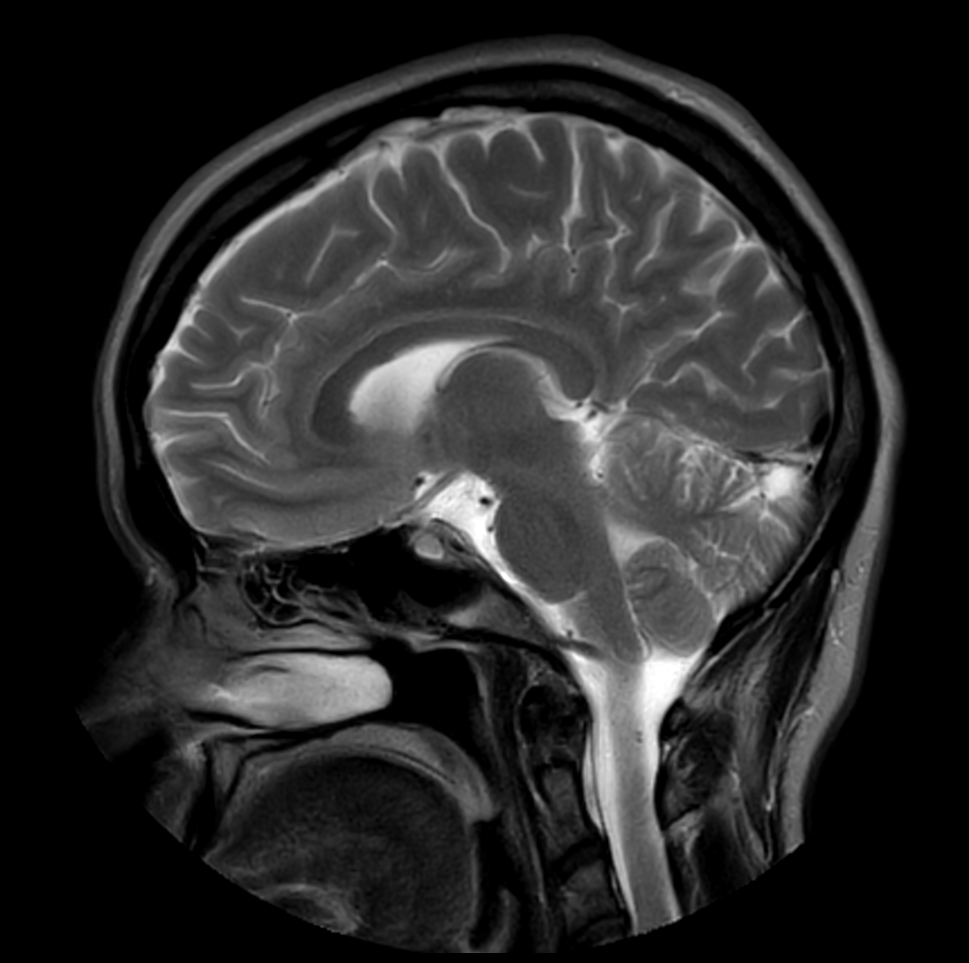

Sagittal T2w TSE MultiVane XD